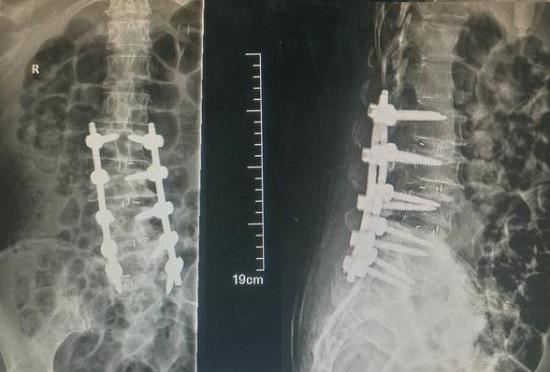

针对腰椎侧凸和腰椎退变实施的腰椎融合术